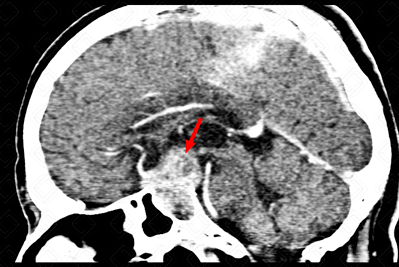

Descrição das figuras: Tomografia computadorizada do crânio pós-contraste evidenciando lesão intrasselar, com extensão suprasselar (formato em 8), com ávida captação pelo meio de contraste, envolvendo os seios cavernosos, de forma mais evidente à direita (setas vermelhas).

Macroadenoma hipofisário: Grupo de lesões pertencentes aos adenomas hipofisários, sendo neoplasias caracteristicamente com seu surgimento intrasselar. Os adenomas hipofisários dividem-se em: microadenomas (lesões com 10 mm ou menos) e macroadenomas (lesões superiores a 10 mm, apresentando na maioria dos casos componente suprasselar). [cms-watermark]

O adenoma hipofisário com extensão suprasselar (ou macroadenoma) tem aspecto de uma "figura de 8" ou boneco de neve, pois é suavemente comprimido ao nível do diafragma selar. Corresponde a cerca de 33-55% das massas suprasselares nos adultos.

Aspectos de imagem: Como já dito acima, são lesões intra e suprasselares, com aspecto em 8 ou boneco de neve e que realçam fortemente e de forma heterogênea pelo meio de contraste. As calcificações são raras. Na ressonância magnética, o sinal da lesão é variável, mas, na maioria dos casos, seu sinal é semelhante à substância cinzenta nas sequências (figuras acima). Pode existir presença de nível líquido nas apoplexias.

Pode ser muito agressivo com erosão do assoalho selar, invasão do seio cavernoso e envolvimento da carótida interna.